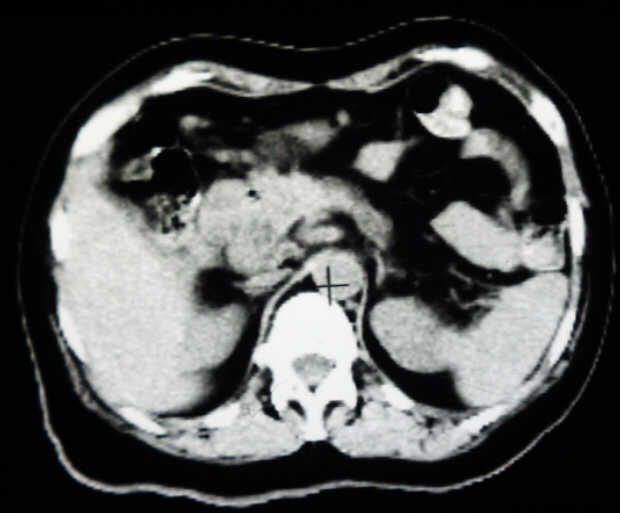

Pancreatic Head Mass: What Can Be Done?

Diagnosis: Angiography

Giuseppe Morelli Coppola, Raffaella Niola, Franco Maglione

Unità Operativa di Radiologia Vascolare ed Interventistica, Azienda Ospedaliera "A. Cardarelli". Napoli, Italy